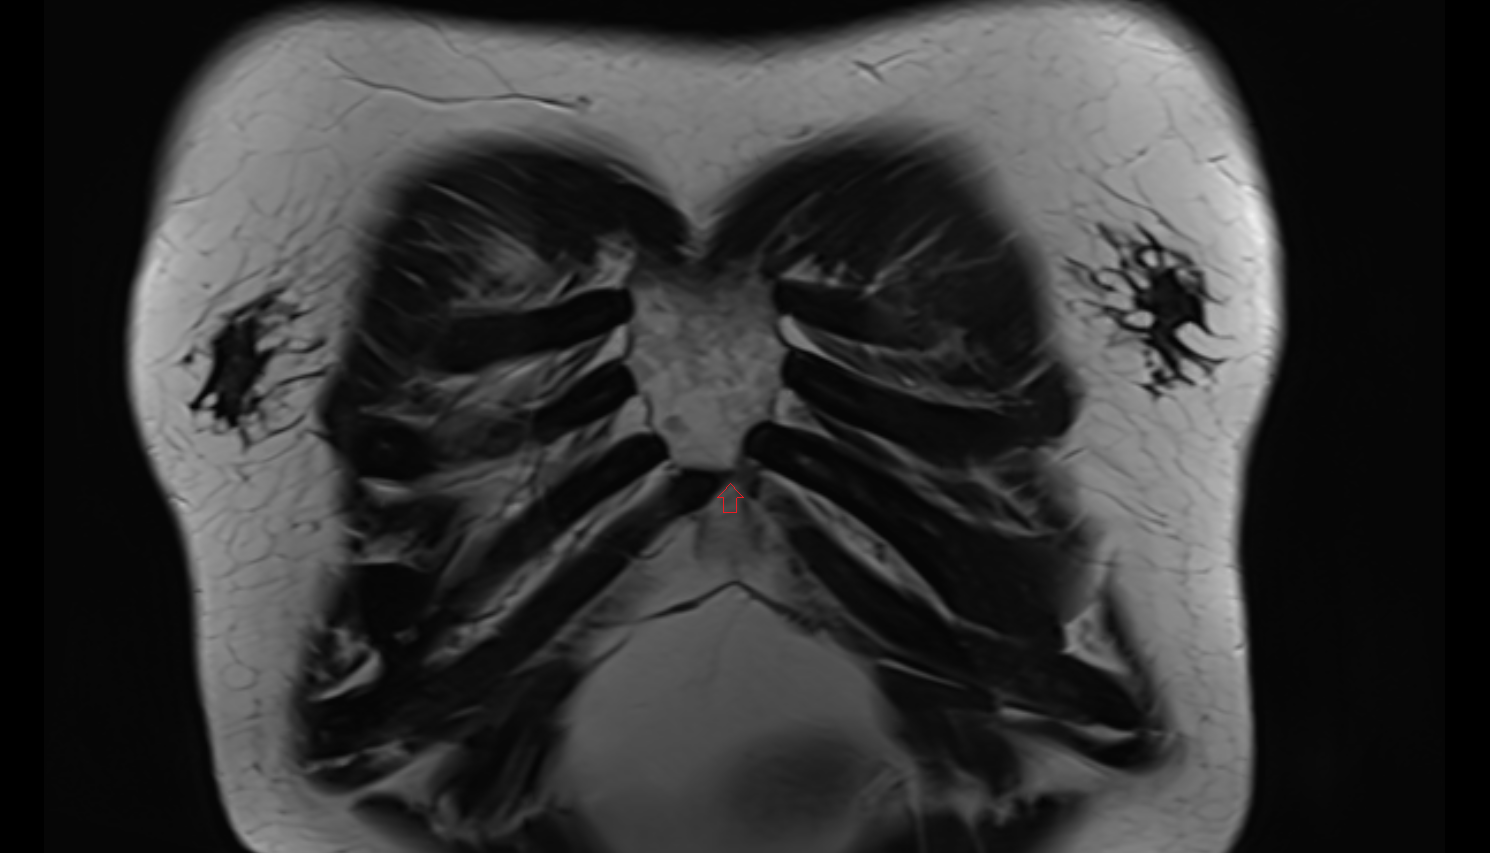

- Manubrium of sternum

- Body of sternum

- Xiphoid process of sternum

- Sternum

- Costal cartilages

- Costal notches

- Costochondral joints

- Sternocostal joint

- Sternocostal synchondrosis of first rib